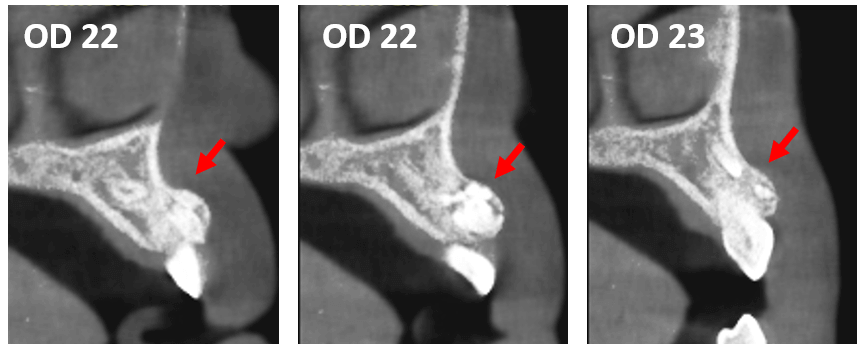

Fig.2

En cortes transaxiales (Fig.2) y en cortes axiales (Fig.3) de los órganos dentario 22 y 23, se observan el aumento de volumen por vestibular condicionando el adelgazamiento y aparente erosión de la cortical vestibular condicionado por el objeto de densidad mixta, a predominio hiperdensa, en la cual se observan múltiples focos de densidad variable, ovalados y alargados, los cuales se asemejan a múltiples dentículos (dientes pequeños).